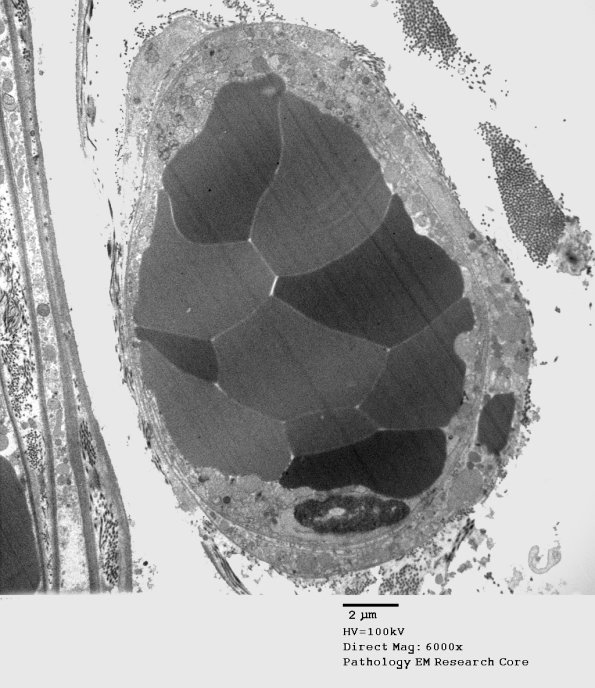

This appears to be a microthrombus. (electron micrograph)